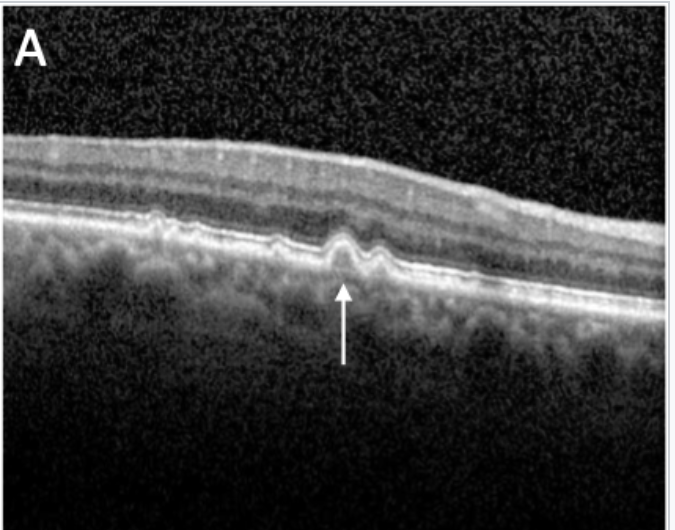

What is this?

A

Pigment epithelium detachment (PED)- when RPE is separated from bucks membrane

on an OCT it looks like a dome shaped elevation of the RPE